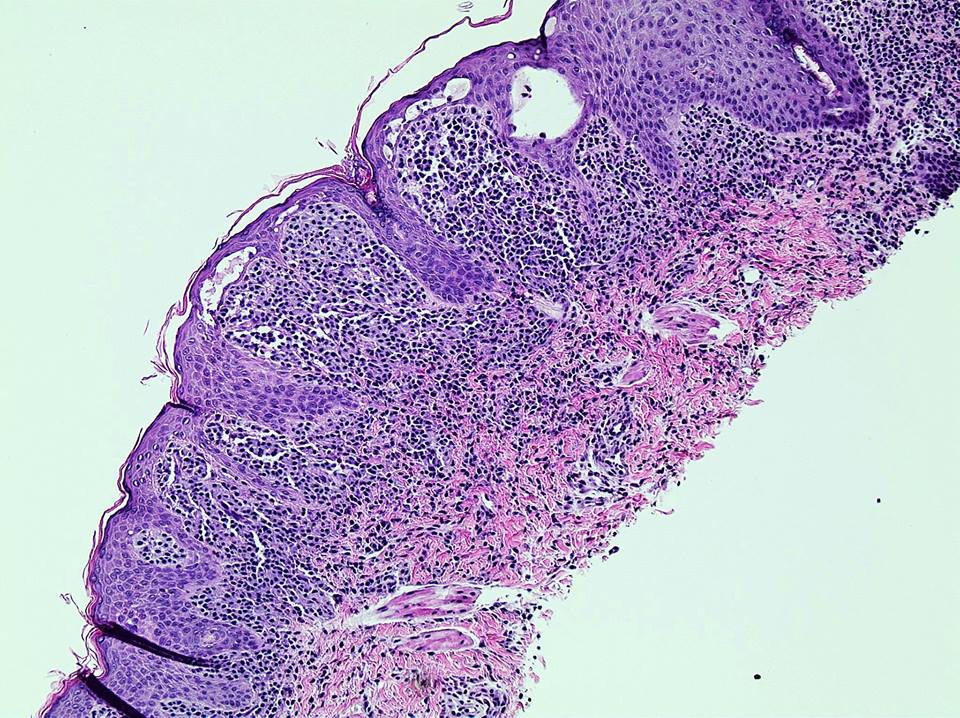

Microscopic (histologic) description

- Within the macules and plaque, mast cells are predominantly in papillary dermis

- Mast cells are round or spindle shaped with abundant eosinophilic cytoplasm, distinct cytoplasmic boundaries, large pale nuclei

- Eosinophils are often present

- Also edema of papillary dermis, subepidermal vesiculation

Microscopic (histologic) images